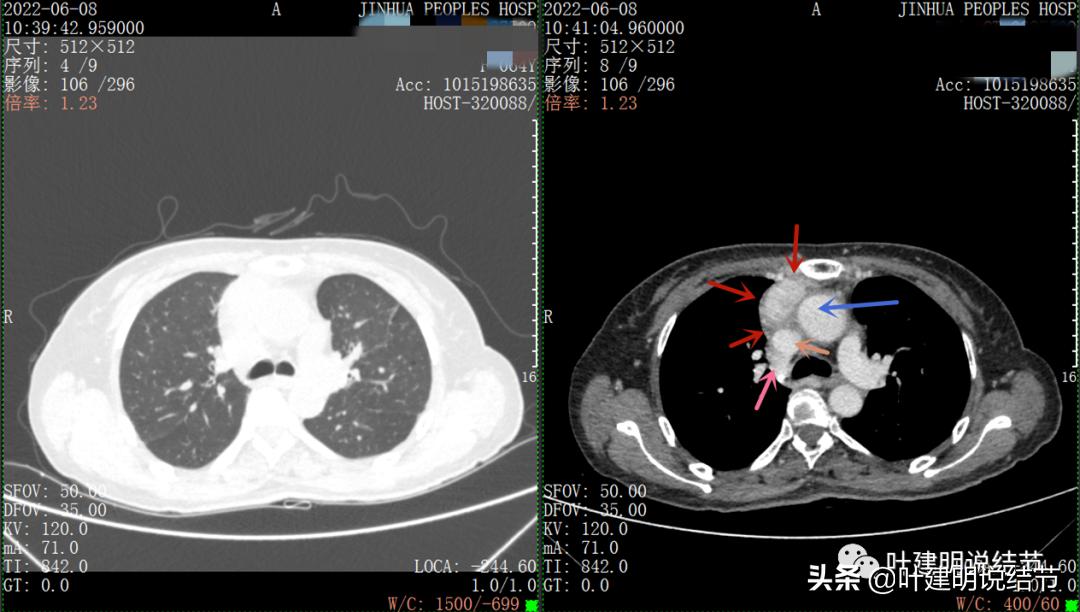

以下图片左侧是肺窗,右侧是纵隔窗。红色箭头示病灶,桔色箭头示无名静脉,黄色箭头示支气管,砖色箭头示上腔静脉,蓝色箭头示主动脉,紫色箭头示肺动脉。

病灶纵隔胸膜侧非常光滑,说明来源于纵隔

粉色箭头示淋巴结可能